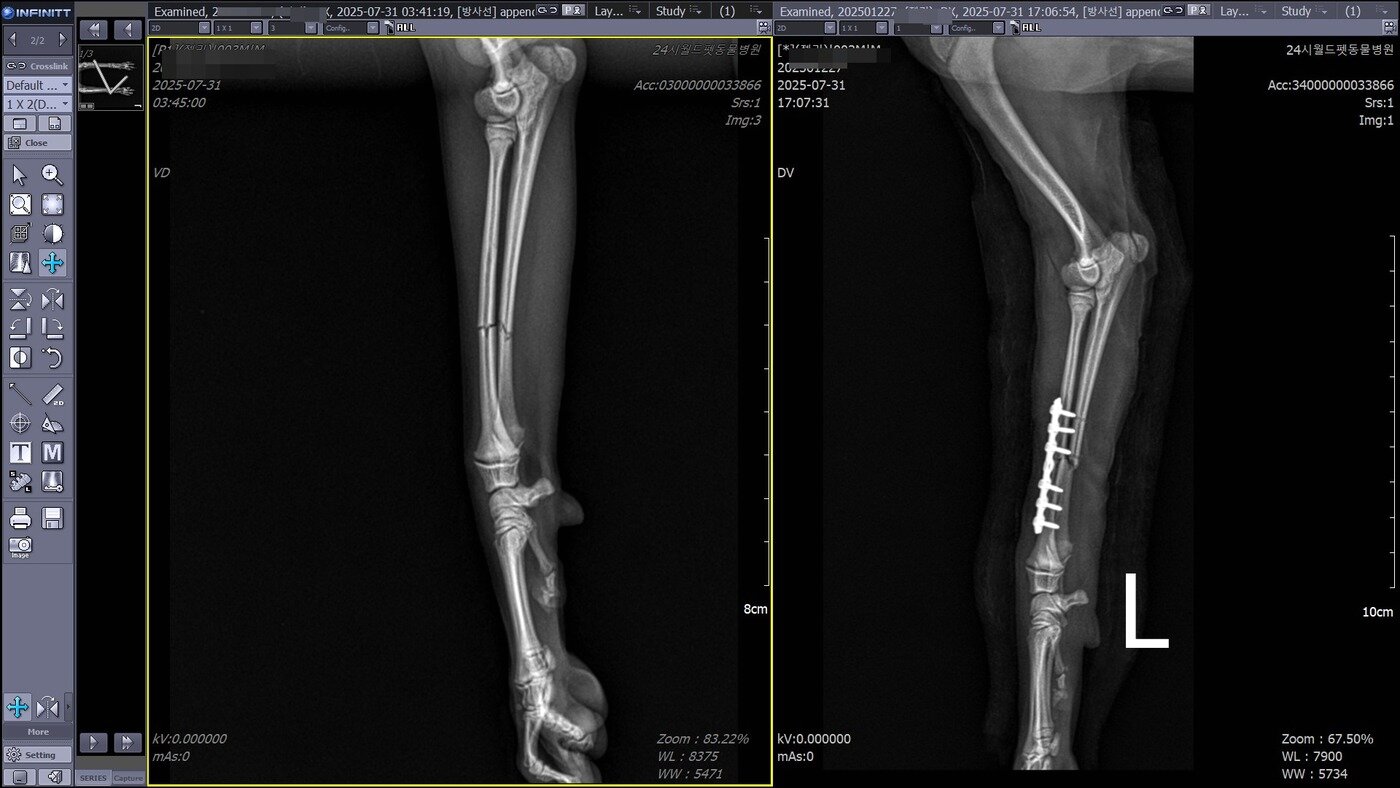

본문 이미지 - 골절 수술 전 후 방사선 사진(동물병원 제공) ⓒ 뉴스1

골절 수술 전 후 방사선 사진(동물병원 제공) ⓒ 뉴스1